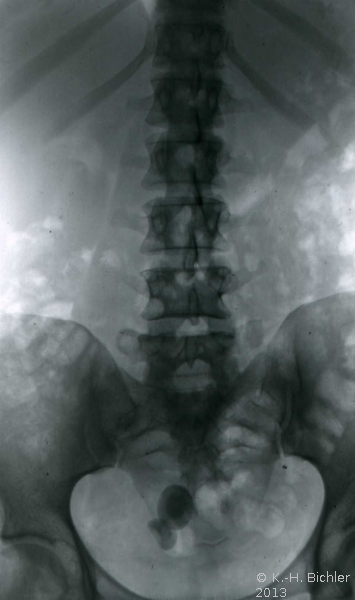

Die Ureterozele kann auch trotz Komplikationen (Harnsteinbildung) und schwersterster Abflussbehinderung lange Zeit unerkannt bleiben (rezidivierende Harnwegsinfekte) wie bei dieser Erwachsenen mit sekundärem Megaureter bei steintragender Ureterozele rechts und rezidivierendem Harnwegsinfekt (Abbildung 3) (

KasuistikKasuistikBei dieser 54jährigen Frau fand sich ein sekundär-obstruktiver Megaureter bei Ureterozele mit Harnsteinbildung. Jahrelang rezidivierende Harnwegsinfekte ohne entsprechende Abklärung. Therapie: Schlitzung der Ureterozele und Harnsteinentfernung (s. Abbildung 3).).